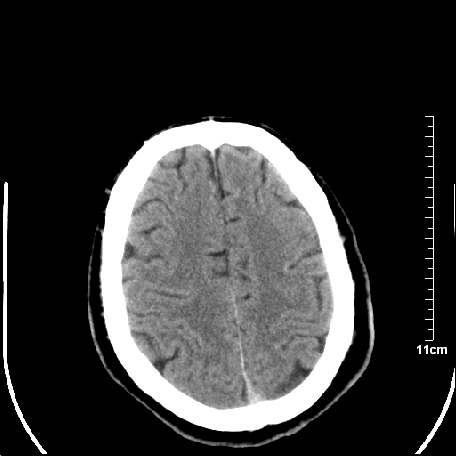

外伤患者,什么病,

外伤患者,没什么症状,

颅内未见明显创伤性影像,建议上传骨窗,看看左侧颧弓

未见明显异常改变。

靠,老年脑,没什么病。

无明显异常发现.